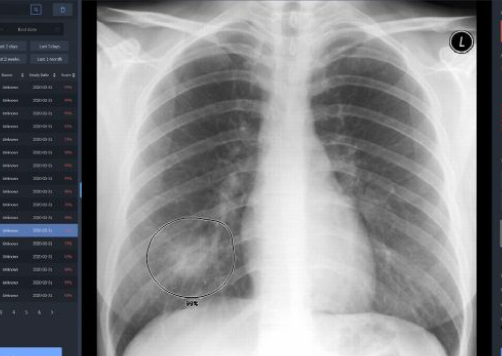

전리방사선 및 비전리방사선의 취급과 방사성동위원소를 이용한 행의학검사와 초음파검사 등 관리 및 취급 업무를 하는 사람을 말합니다. 보통 병원에 가서 엑스레이 검사를 하거나, CT, MRI 검사를 하는 사람들이 방사선사이고, 핵의학과, 방사선종양학과에서 일하는 사람도 방사선사입니다.